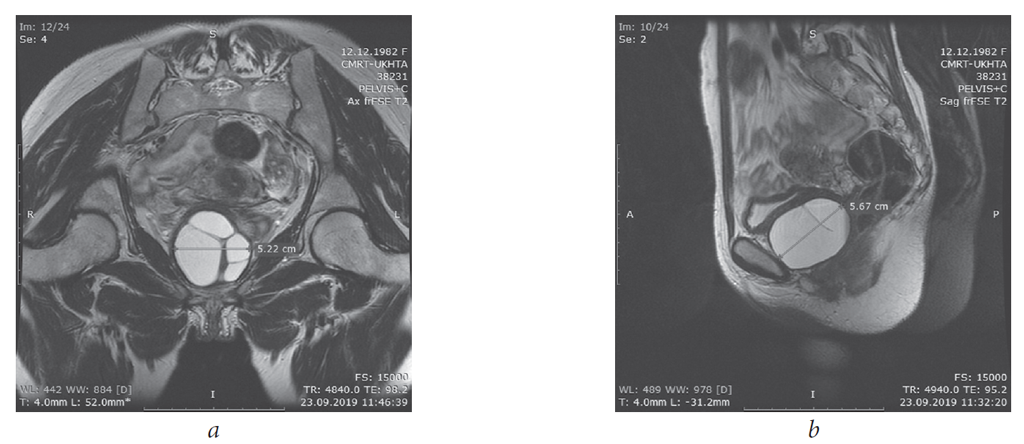

Magnetic resonance imaging (MRI) of the pelvic organs showed an uneven contour of the lower wall of the bladder, with uneven accumulation of the contrast agent, and with an altered MR signal. Fatty tissue of the vesicouterine space was viewed satisfactorily. The walls of the vagina, urethra, and the deep transverse muscle of the perineum, a pathological zone with a heterogeneous MR signal, uneven accumulation of contrast of 52 × 50 × 56 mm in size with moderately thickened septa that do not accumulate contrast are visualized in the projection of the lower wall of the bladder (Fig. 1 a, b). The visualized sections of the coecum and rectum had no abnormalities. The adipose tissue of the pararectal region and the ischiorectal fossa had no abnormalities. Free liquid in the study area was not detected. Pathologically, altered lymph nodes in the study area were not conclusively visualized.

Fig. 1.Patient M., 36 y. o. MRI of the pelvis. Paraurethral cyst, axial size 52 mm (a), sagittal size 52 mm (b)

Рис. 1.Пациентка М., 36 лет. Магнитно-резонансная томография малого таза. Парауретральная киста 52 мм в аксиальном размере (a), 56 мм — в сагиттальном размере (b)